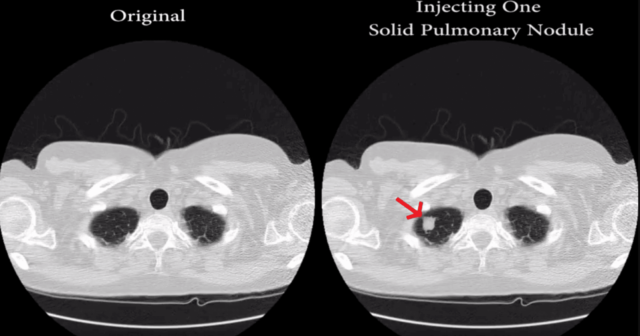

CT-GAN, questo il nome del framework malevolo ideato dagli esperti israeliani, è basato sugli algoritmi di machine learning di una rete nota come Generative Adversarial Network (GAN) – la stessa, per dire, adoperata per generare volti, gattini e altri contenuti fasulli che al momento spopolano fuori e dentro il Web.

Piuttosto che limitarsi ai volti e ai gattini di cui sopra, CT-GAN è stato addestrato a generare noduli tumorali all’interno delle analisi radiologiche dello stato dei polmoni: 70 di queste analisi sono state contraffatte, quindi fornite a tre diversi radiologi che nel 99% dei casi hanno confermato la diagnosi di cancro nonostante i noduli fossero opera della IA. Sulle analisi in cui CT-GAN aveva rimosso i tumori realmente esistenti, i suddetti radiologi hanno confermato la (finta) guarigione nel 94% dei casi.